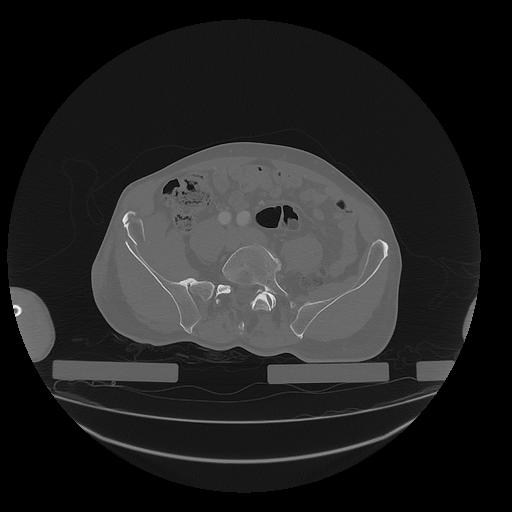

31 PULMON,CE,Vol,1.0,PULMON,,